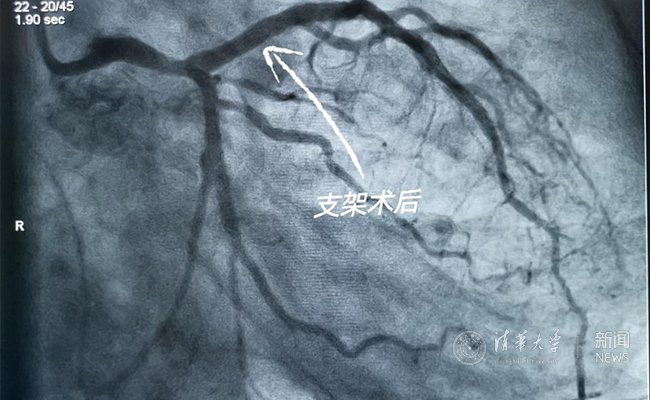

2019.05国产冠脉生物可吸收支架在新葡萄官网AMG第一附属医院正式启用

作为北京地区首家正式引入国产冠脉生物可吸收支架单位,5月20日,新葡萄官网AMG第一附属医院(北京华信医院)心脏中心主任苗立夫团队顺利完成该院首例生物可吸收支架植入。